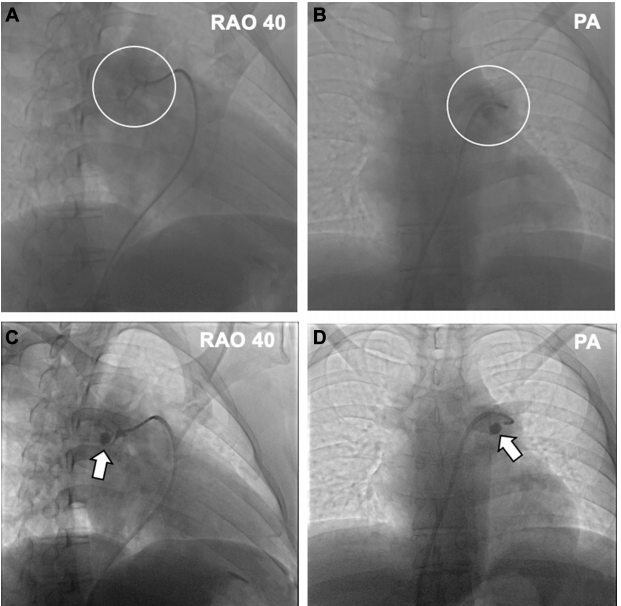

为明确咯血原因,我们进行了肺动脉造影。未发现明显的肺动静脉畸形、闭塞或造影剂充盈缺损。尽管操作谨慎,患者仍突发剧烈咳嗽及咯血,咯出约 20mL 纯血。肺动脉造影显示造影剂外渗(下图A 和图 B)及一个人工假性动脉瘤(图C 和图D)。随即对受累血管进行了明胶海绵栓塞,咯血逐渐停止。